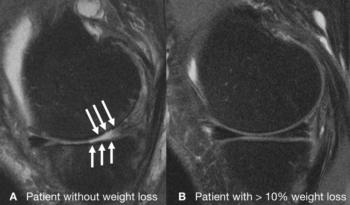

Figure 2. Knee joint of a patient without weight loss (A) showing severe cartilage defects after 48 months, and intact knee joint of a patient with a substantial amount of weight loss (B).

Cartilage degeneration was significantly lower in the weight loss group, compared to the control group over the 96 months. However, this finding was only present among the patients who lost weight through diet and exercise or diet alone. Although patients who only exercised lost as much weight as patients who dieted alone or dieted and exercised, weight loss through exercise alone showed no significant difference in cartilage degeneration, compared to the group who lost no weight.